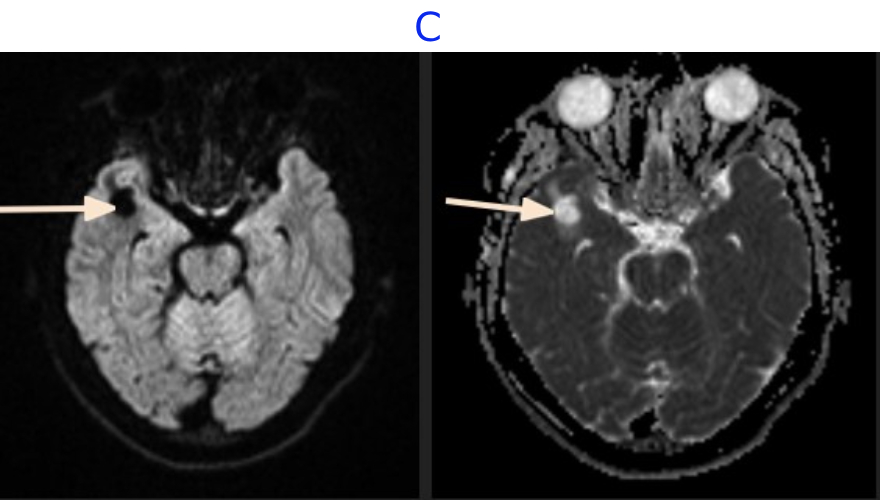

B. FINDINGS - MR BRAIN

• B. FLAIR sequence demonstrates mild perilesional edema in the right anterior temporal lobe.Post contrast T1 demonstrates no enhancement and M2 segment of right MCA indenting the antero-superior pole of the lesion